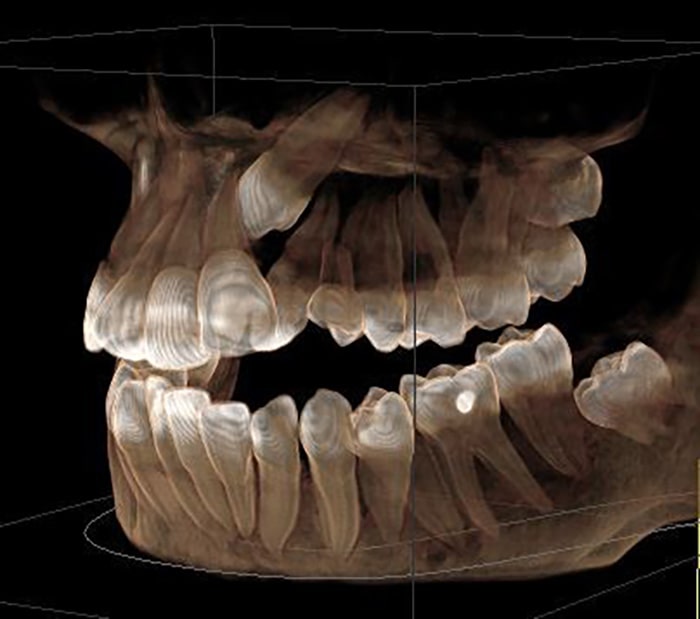

At Kamala Dental Super Speciality Hospital, Thiruvananthapuram, we utilize advanced Cone Beam Computed Tomography (CBCT) and 3D scanning technologies to obtain highly detailed images of your teeth, jaws, nerves, and surrounding structures. These cutting-edge tools empower our team to diagnose more accurately and plan treatments with greater precision - giving you safer, more predictable outcomes.

- Detailed, Clear Views: CBCT produces 3D images of bone anatomy, root canals, jaw joints, sinuses, and nerve pathways - far more informative than traditional 2D X-rays.

- Assessment of bone density and structure

- Orthodontic treatment analysis & simulation

- 3D Reconstruction: Software assembles images into a precise 3D model of your oral structures.